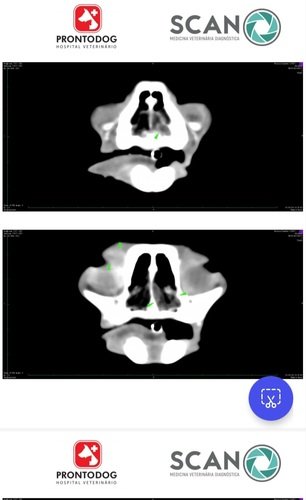

Já foi feito uma tomografia do crânio para saber a dimensão do tumor.

Ela vaí ter que passar por uma cirurgia para retirar todo o olho esquerdo, fazer eletroquimioterapia , tirar o linfonodo esquerdo do pescoço ( que está aumentado) e fazer uma rinoscopia da narina (que apresenta um processo infeccioso ). E terá que ficar 2 dias internada.